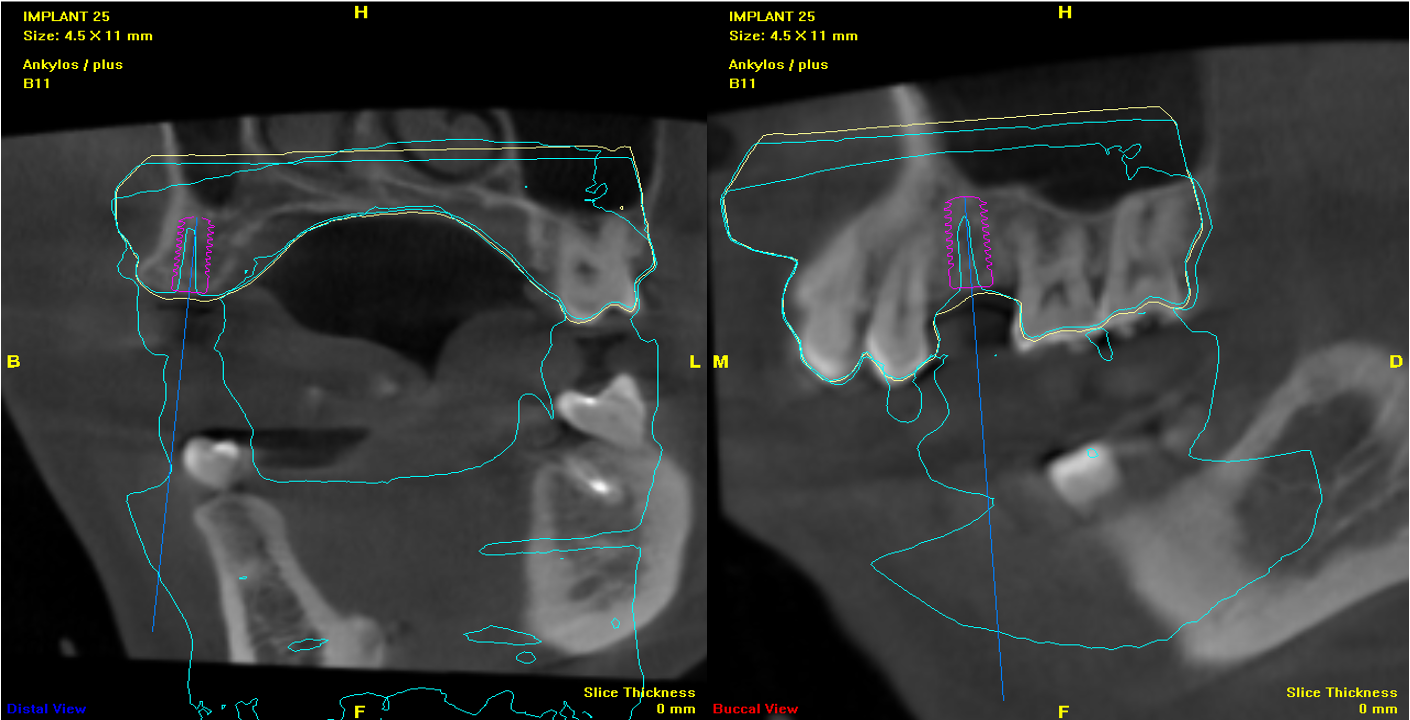

植牙用手術定位器

植牙位電腦斷評估

電腦定位手術導板